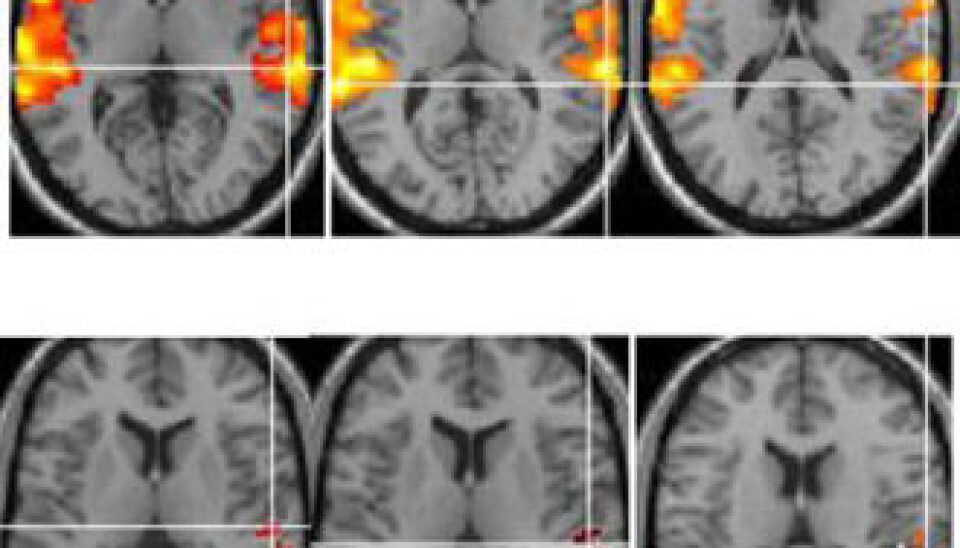

Hugdahl’s research group has made use of a variety of neuroimaging techniques, including functional magnetic resonance imaging technology (fMRI) to enable them quite literally to see what happens inside the brain when the inner voices make their presence known.

Images of patients’ brains reveal a spontaneous activation of neurons in a particular area of the brain – specifically the rear, upper region of the left temporal lobe. This is the area responsible for speech perception, and when healthy people hear speech it becomes activated. So what happens when patients with schizophrenia hear a real voice and a hallucinatory one at the same time?

“It would be natural to assume that neural activity would increase somewhat – even twofold. But quite the opposite takes place; we actually observed that the activity ceased altogether,” states Hugdahl.